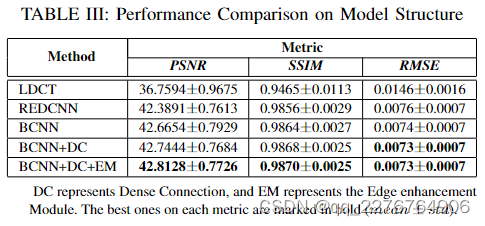

1)结构和模块:为了探究EDCNN模型各组成部分的作用,我们对结构进行了分解实验。 首先,我们设计了一个基本模型(BCNN),从图1所示的结构中去除了密集连接和边缘增强模块,然后添加了密集连接(BCNN+DC)和边缘增强模块(BCNN+DC+EM, EDCNN)依次。 为了充分展示模型的潜在能力,所有模型都使用相同的训练策略进行 MSE 损失训练。

图 5 显示了 PSNR 曲线,在每个时期对训练模型的测试集进行测试。 我们还添加 REDCNN 作为比较。 值得注意的是,我们设计的基本模型(BCNN)已经取得了比 REDCNN 更好的性能。 并且通过添加密集连接和边缘增强模块,PSNR的值将不断增加。 此外,边缘增强模块加速了模型的收敛过程。 在表中。 III,我们可以检查这些模型的 PSNR、SSIM、RMSE 值。 完整的 EDCNN 模型在这些指标上具有最佳结果。